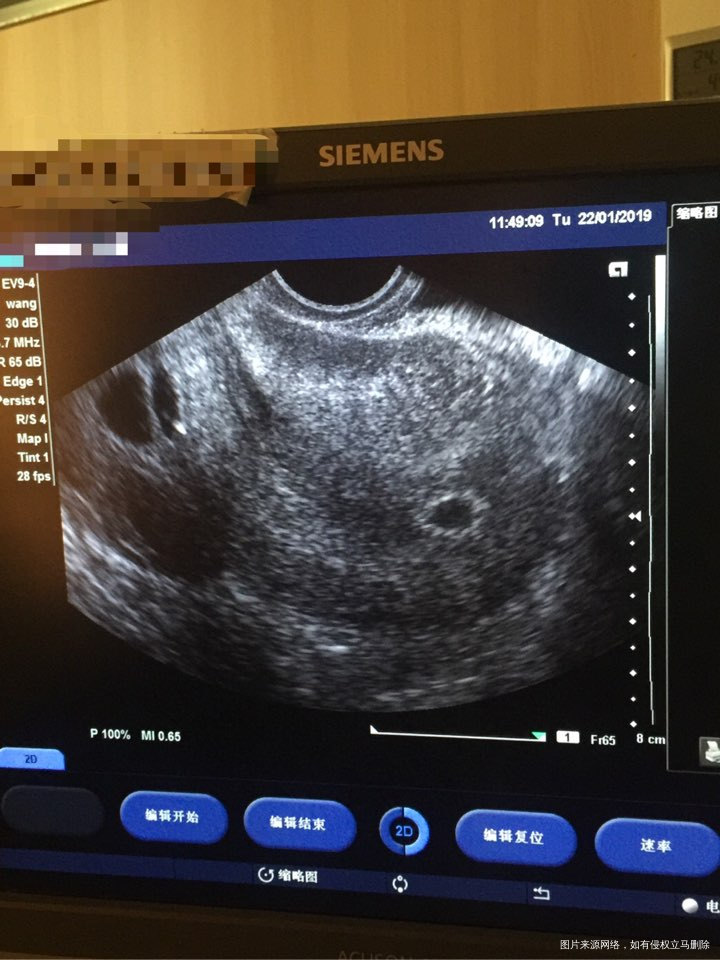

1楼5千多的hcg,按照时间,确实偏低了,不过可以再看一周,如果血值继续升高,就有希望,万一血值下降了,就放弃吧,加油💪

🏝 回复 姚观昀:如果下降了要怎么放弃好点呢?

2楼您好,继续用药两天,血值确实有点低,隔日复查看看血值情况,如果不升反而降,建议放弃,放平心态,同时注意休息不能劳累,继续口服叶酸片至孕后满三个月预防胎儿神经管畸形,注意保暖不能受凉,加强营养饮食以清淡为主多吃高蛋白的食物,不能吃辛辣油腻刺激性的食物,一个月内禁止同房,注意局部卫生,不能坐浴,先调理好身体这是主要的,祝健康好孕!觉着我的回复对您有帮助,请点采纳,谢谢你了!

🏝 回复 刘东学:如果血值不高,采取怎么样放弃好?